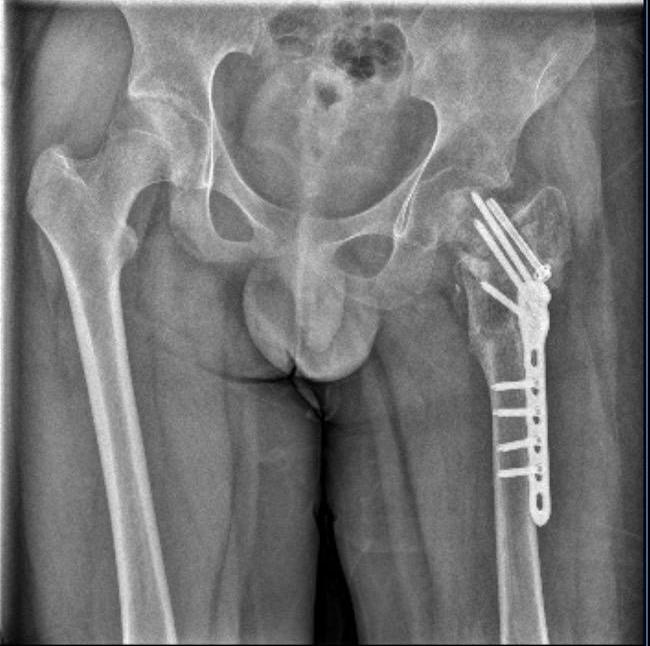

7月,晋江市公安局对小武被故意伤害一案立案侦查。随后,晋江市公安局对小武进行了人体损伤程度鉴定,8月29日出具的《鉴定意见通知书》显示,小武三个部位不同程度损伤,其中,“左髋部重伤二级,胸部轻伤一级,双下肢轻微伤”,同时,其左股骨打了钢针、钢板。